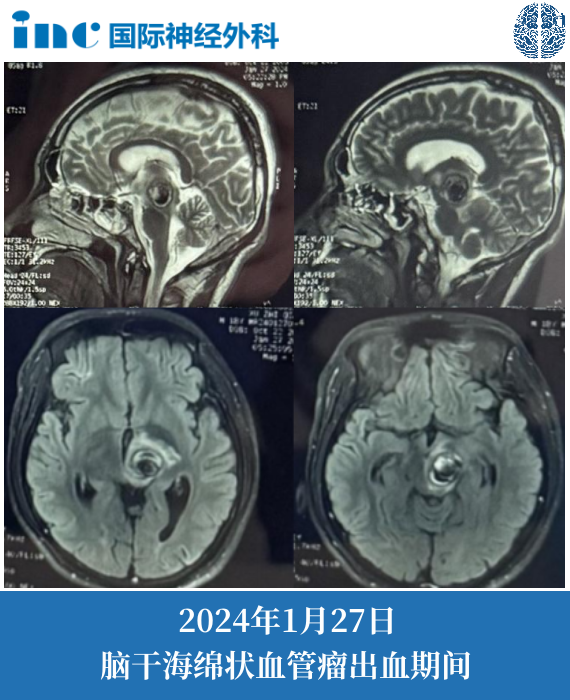

18岁男孩小林,在父母的精心照顾下,正在住院中。而此刻一家人在病房,与巴教授进行视频咨询。2023年6月,小林一开始脑干海绵状血管瘤出血,症状较轻,表现为右侧手臂和腿部麻木,面部麻木,可以正常行走。保守治疗,休息几天之后症状减轻,能正常上学。2024年1月,小林再次出血,右侧胳膊出现明显麻木,腿部无力,不能行走。一直住院观察……

这里附上患者的相关影像截图,2024年1月27日的核磁共振成像。考虑到自2023年年中以来的病史以及二次严重出血,有明确的手术指征。